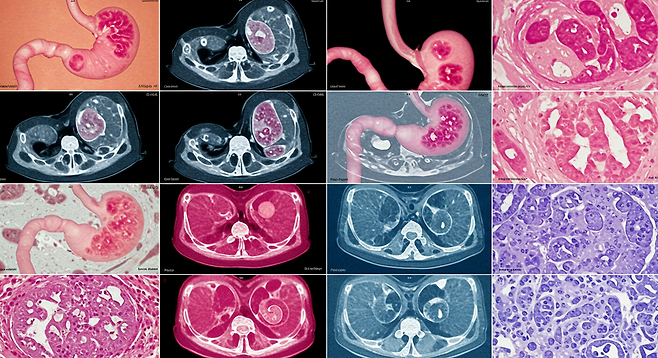

위암은 한국인에게 매우 흔한 암으로, 남성에서는 발병률 1위, 여성에서는 4위를 차지하는 중요한 건강 문제입니다. 조기에 발견하면 생존률이 90~95%에 이르는 만큼, 정기적인 내시경 검진과 함께 위에 부담을 주는 음식을 피하는 것이 중요합니다.